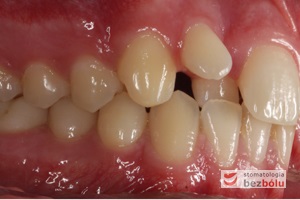

Młody 28-letni, pogodny, stale uśmiechnięty pacjent zgłosił się celem korekcji wad zębowych ograniczających pełną ekspresję uśmiechu. Głównym problemem był dodatkowy siekacz boczny (dwójka) po stronie prawej w łuku górnym. Dodatkowy ząb spowodował stłoczenia pozostałych zębów w łuku górnym oraz przesunięcie linii pośrodkowej. Obliczenia dostępnego miejsca dla siekacza bocznego wpłynęły na wybór zęba przeznaczonego do ekstrakcji. Usunięto dwójkę ustawioną dowargowo, zaś jej „siostrę bliźniaczkę” skierowaną w stronę podniebienia wprowadzono do łuku zębowego w drodze leczenia ortodontycznego. Problemem było szczelne zamknięcie szpary poekstrakcyjnej z powodu nadmiaru miejsca w kości. Wyrównano linię pośrodkową. Leczenie przeprowadzono jednym łukiem ortodontycznym górnym, dolny łuk zębowy nie wymagał założenia aparatu. Po zdjęciu zamków korekcję detali przeprowadzono z użyciem pozycjonera wykonanego w technice termoformingu. Stabilizację efektów leczenia zapewnił stały retainer klejony do powierzchni podniebiennych siekaczy górnych.